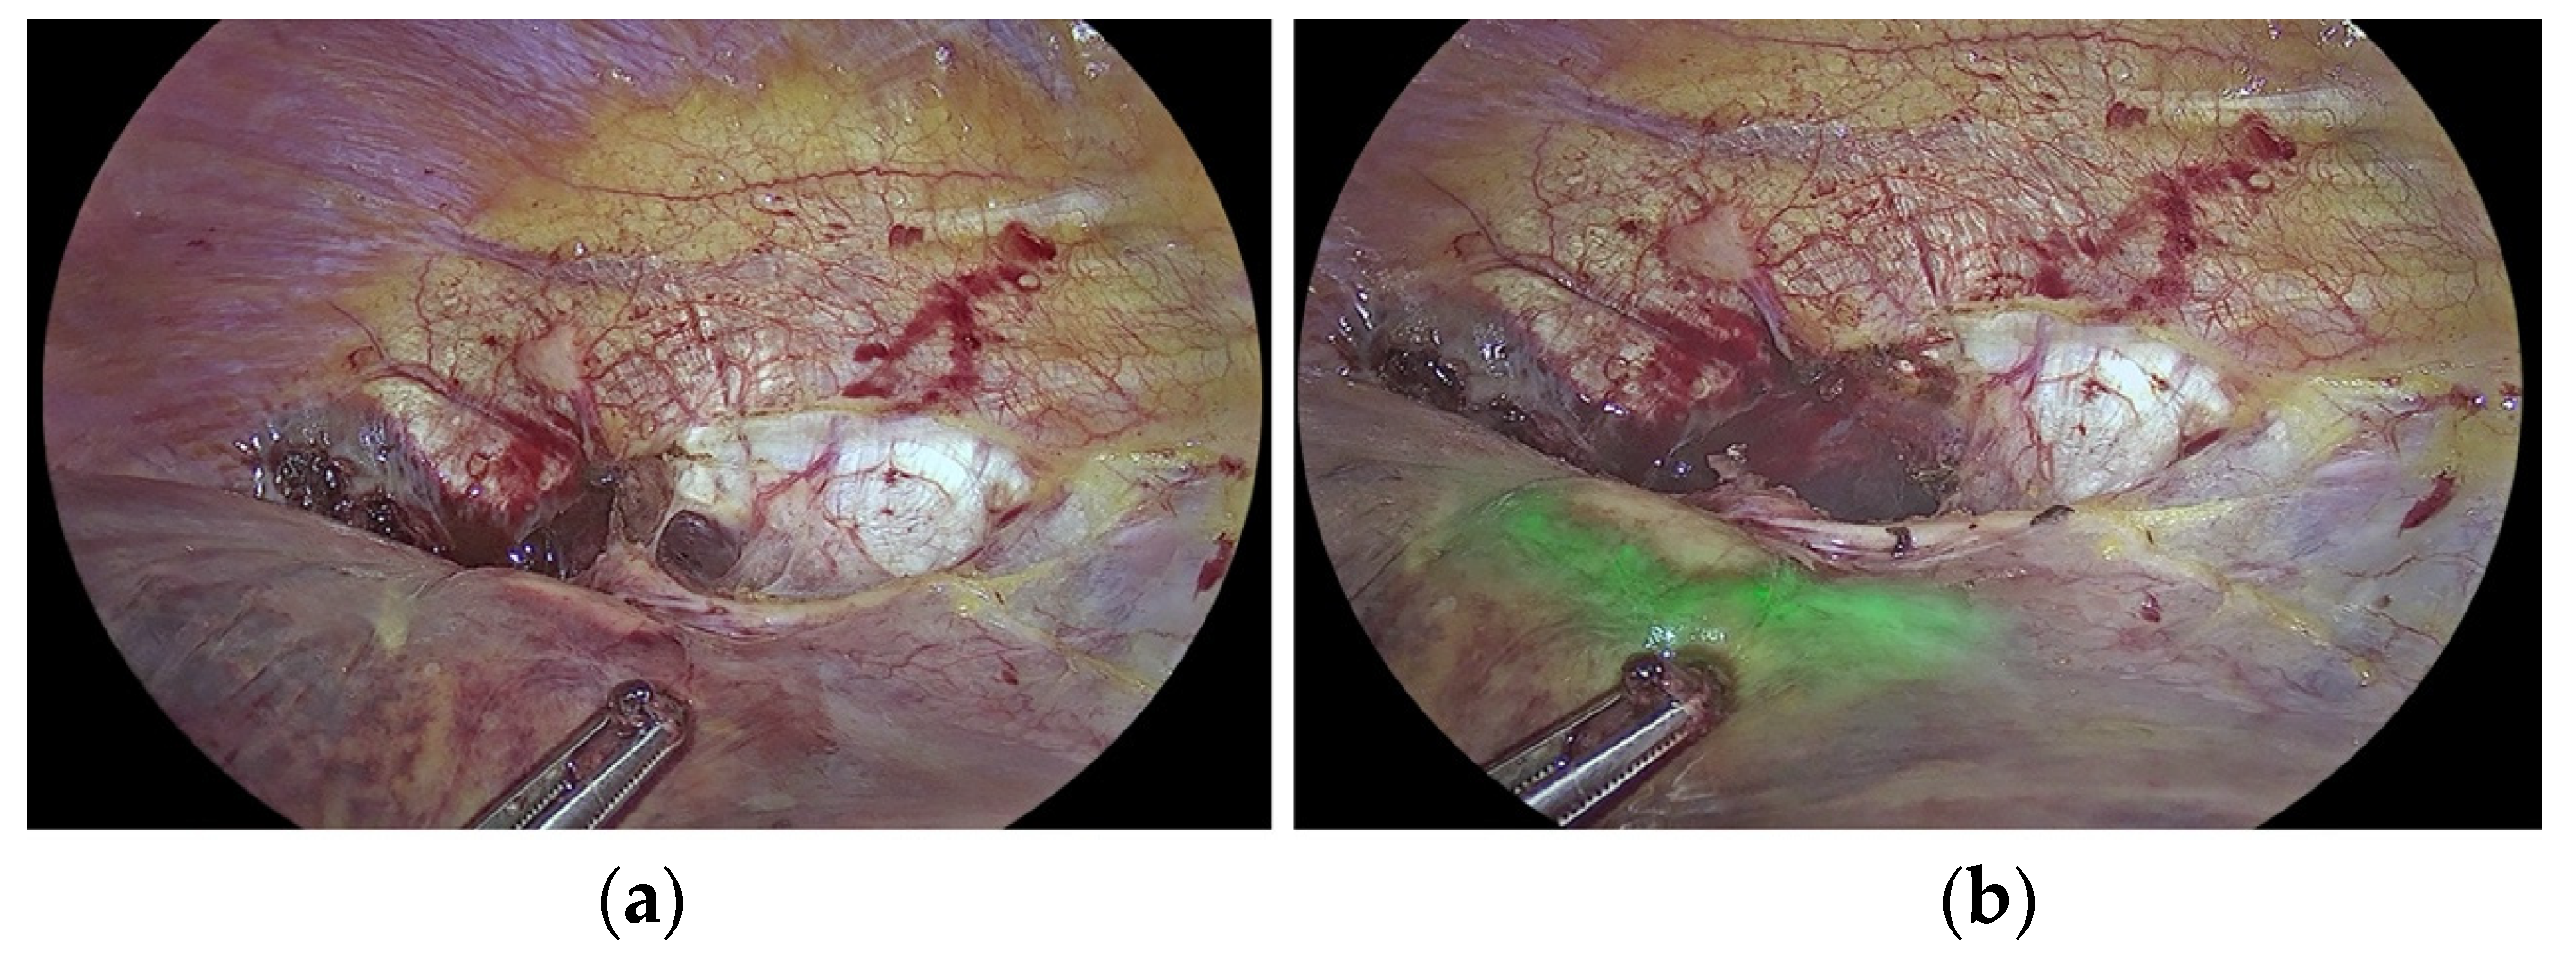

3.2. Improving the Detection of Cancer Tissue and Targeted Treatment

- Raimondo, D.; Maletta, M.; Malzoni, M.; Cosentino, F.; Scambia, G.; Falcone, F.; Coppola, M.; Turco, L.C.; Borghese, G.; Raffone, A.; et al. Indocyanine green fluorescence angiography after full-thickness bowel resection for rectosigmoid endometriosis: A multicentric experience with quantitative analysis. Int. J. Gynecol. Obstet. 2021, 158, 679–688. [Google Scholar] [CrossRef]